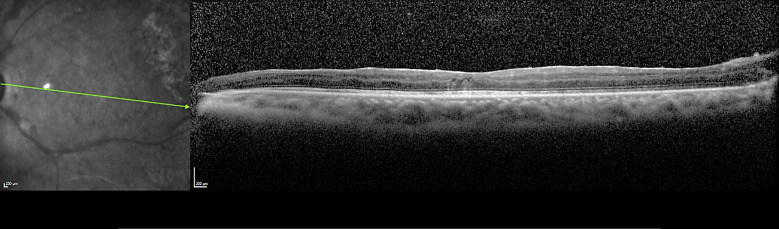

Case presentation: A 49-year-old male with human immunodeficiency virus (HIV) infection presented with fever and cough, accompanied by acute bilateral vision reduction, photophobia, and eye pain. Clinically, his examination showed severe panuveitis in both eyes. Investigations showed elevated white blood cells, C-reactive protein, cluster of differentiation 4 count of 180/μL, HIV viral load of <40 copies/mL, and unexpectedly, aqueous and blood cultures were negative. An autoimmune workup was also negative. Given this, intravitreal antibiotics were administered alongside systemic antibiotics. Subsequent chest computed tomography showed pulmonary cavitations and liver lesions, and despite negative culture results, a 16S rRNA RT-PCR of the aqueous humor detected Klebsiella pneumoniae genetic material. The patient completed 6 weeks of ceftriaxone and multiple bilateral vitrectomies for recurrent retinal detachments, likely due to retinal necrosis.